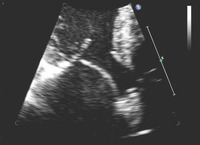

Regurgitação mitral

Corte apical de 4 câmaras de folheto mitral posterior instável

Do acervo de Samir Kapadia e Mehdi H. Shishehbor